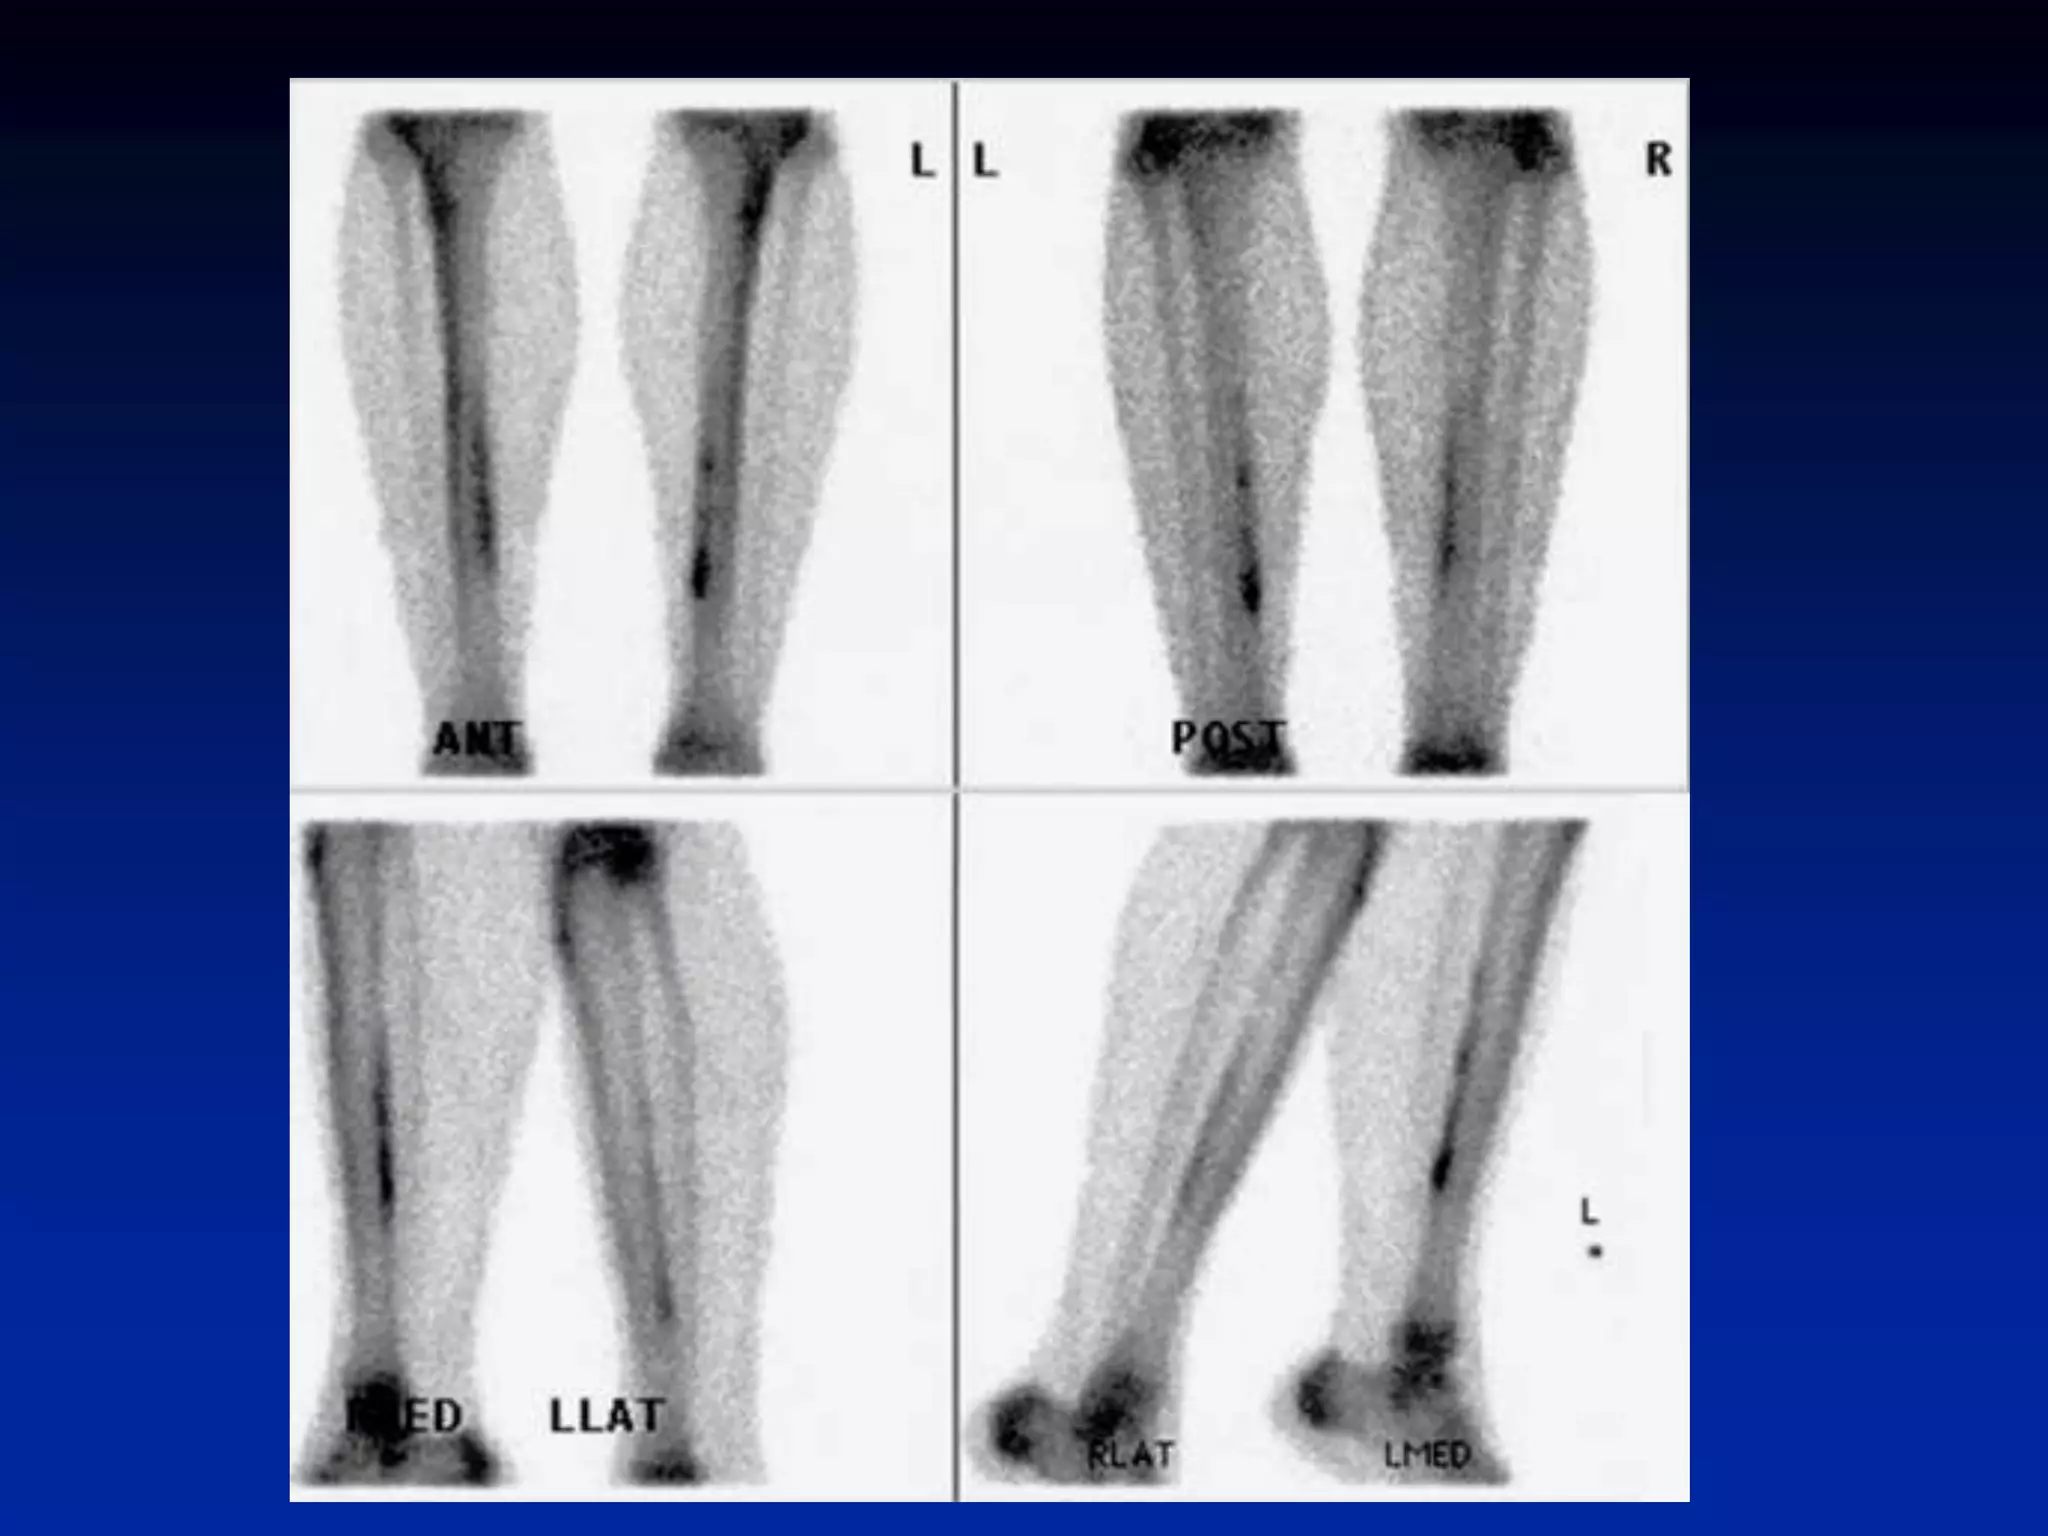

Shin Splints (Periostitis)

• exercise induced pain along medial or

posteromedial aspect of tibia

• associated with increased tracer uptake

• >1/3 of bone length

• middle to distal tibia

• usually bilateral (not necessarily symmetrical)

• microperiosteal tears (via Sharpey’s fibers)

• positive finding does not predict further injury

• Hyperperfusion and hyperemia are

typically present in acute stress fracture.

• Unlike in stress fractures, angiograms and

blood pool images are usually normal in

shin splints. Delayed bone images reveal

longitudinally oriented linear areas of

increased uptake of varying intensity that

involve one-third or more of the posterior

tibial cortex

Shin Splints (Periostitis) •exercise induced pain along medial or posteromedial aspect of tibia • associated with increased tracer uptake • >1/3 of bone length • middle to distal tibia • usually bilateral (not necessarily symmetrical) • microperiosteal tears (via Sharpey’s fibers) • positive finding does not predict further injury

• Hyperperfusion andhyperemia are typically present in acute stress fracture. • Unlike in stress fractures, angiograms and blood pool images are usually normal in shin splints. Delayed bone images reveal longitudinally oriented linear areas of increased uptake of varying intensity that involve one-third or more of the posterior tibial cortex